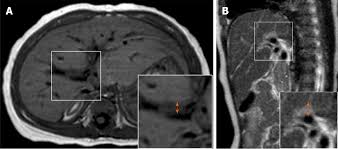

Biliary atresia (ba) is the destructive inflammatory obliterative cholangiopathy of neonates. Left untreated or with failure of the kasai procedure, biliary atresia progresses towards … The bile duct is a tube that allows the passage of bile from the liver into the gall bladder and, eventually, the small intestine. The mrc of infants with type i and ii of biliary atresia in this study did not show the very thin but patent bile fig4. Imaging features on preoperative ultrasonography (us) and magnetic resonance imaging (mri) were compared between the cba and cc.

On the left we see the normal development of the ductal plate. Divided into fetal / embryonic and perinatal / acquired forms (emedicine: Imaging features on preoperative ultrasonography (us) and magnetic resonance imaging (mri) were compared between the cba and cc. This study compared clinical and radiologic differences between cystic biliary atresia (cba) and choledochal cyst (cc) type ia/b. It is the most common cause of. Hepatocellular cholestasis results from impairment of bile formation and indicates defective functioning of most or all hepatocytes. The body needs bile to aid digestion and carry wastes from the liver out of the body. It is one of the most common causes of neonatal cholestasis, often causing cirrhosis immediately and leading to death and accounts for over half of children who undergo liver transplantation. Increased echogenicity along the anterior. Biliary atresia, also known as extrahepatic ductopenia and progressive obliterative cholangiopathy, is a childhood disease of the liver in which one or more bile ducts are abnormally narrow, blocked, or absent. The diagnosis of biliary atresia could be made with mrc (fig 1b). Biliary atresia imaging accessed 26 october 2017) fetal / embryonic form: Color doppler us findings in neonates and infants by lee and colleagues (1) in the july 2009 issue of radiology.